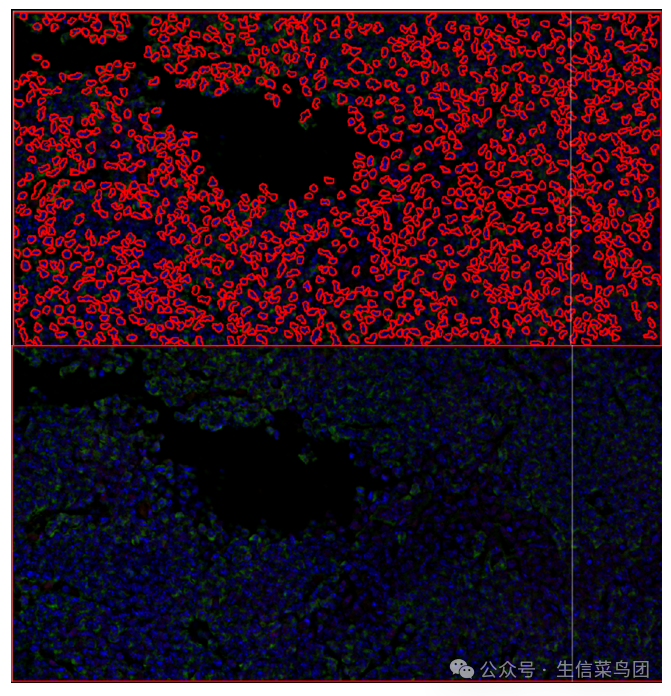

这里要注意,每一个图像中都有运行cell detection后的“红圈圈”,也就是检测到的细胞

图片

应该是上面这样,如果还是像下面那样,就要检查上一步操作,重复看看。